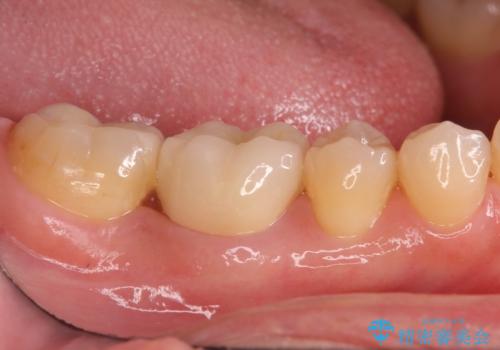

銀歯が取れた セラミックでのやり替え

- 右下奥歯の詰め物が取れたとのことで来院されました。

セラミックでの治療をご希望されましたが、残っている歯が少なかったためクラウンでの治療を行いました。

もう一つ奥の歯に関してもセラミックにやり替えたいとのことでしたので、こちらはインレーでの治療を行いました。